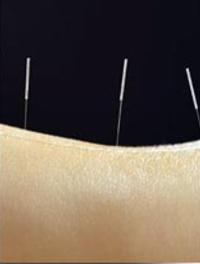

L'efficacité de l'acupuncture dans le traitement de la lombalgie aiguë reste contestée : une synthèse Cochrane de 2005 (1) n'a retenu [...]